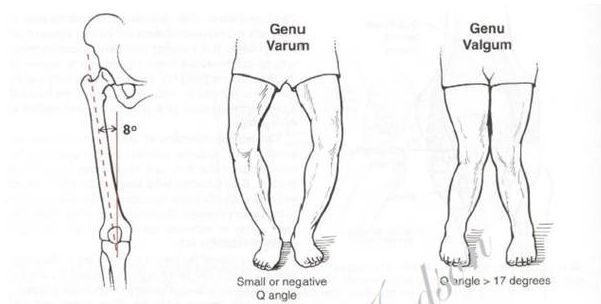

· O/ X 型腿:观察髌骨是否外旋或内旋,外旋则为 O 型腿,内旋则为 X 型腿。O 型腿一般伴随胫骨外旋和 小腿 内翻;X 型腿往往伴随胫骨内旋和 小腿外翻 。下图所示,左侧为 O 型腿,右侧为 X 型腿。

O 型腿:O 型腿有两种,一种是 膝关节 内翻,一种是股骨向内旋转。比较常见的是第二种,即由于 股骨内旋 导致的 O 型腿。正面观察时,两侧膝关节无法并拢,而且膝关节朝向内侧。如下图所示

X 型腿:观察髂前上棘、髌骨和第二 脚趾 头是否在一直线,如下图所示,在髌骨处形成一个夹角,则为 X 型腿; 这个角度若是反方向,则为膝关节内翻造成的 O 型腿。